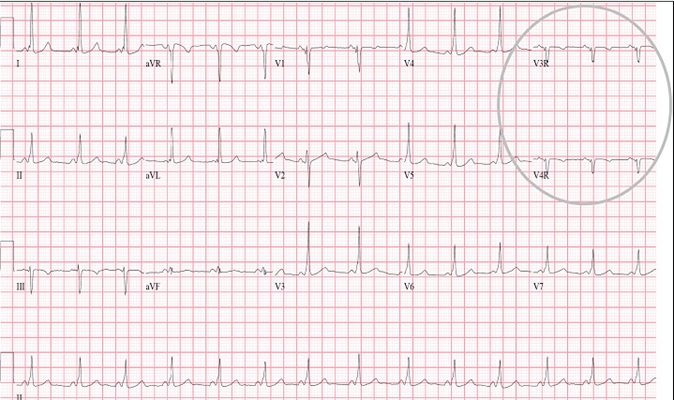

A:預激綜合徵典型的心電圖表現是竇性心搏的PR間期縮短,短於0.12s,而且導聯的QRS波群時間超過0.12s。QRS波群起始部分會有粗鈍,終末部分正常,甚至會導致ST-T波型呈現繼發性的改變,甚至於QRS波群主波方向相反。預激綜合徵是指心房……

A:預激綜合徵是很少見的心律失常,是房室傳導異常的一種類型,提早興奮心室的一部分或全部,引起心室肌提前激動,常合併室上性心動過速。心電圖可見PR間期縮短小於0.12秒;QRS時限延長0.11秒以上;QRS波群起始部粗鈍,繼發性ST-T改變。沒有……

A:預激綜合徵的定義是:因為心房和心室之間存在著異常傳導通路,使部分電活動從心房經過這個通路傳導到心室,引起心室局部心肌細胞發生提前除極,在心電圖上可以出現預激波,這就是預激綜合徵。有預激綜合徵的患者會因這條特殊通路的存在,導致電活動在心房心室……

A:預激綜合徵是房室傳導的異常現象,衝動經附加通道下傳,提早興奮心室的一部分或全部,引起部分心室肌提前激動,合併室上性心動過速發作者稱為預激綜合徵。預激是一種較少見的心律失常,診斷主要靠心電圖。單純預激反應並無明顯症狀。併發房撲或房顫者,心室率……